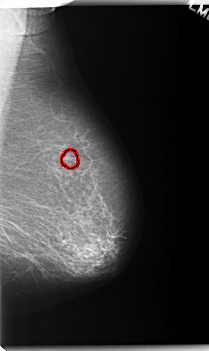

FILE: C_0231_1.LEFT_MLO.OVERLAY

TOTAL_ABNORMALITIES 1

ABNORMALITY 1

LESION_TYPE CALCIFICATION TYPE PLEOMORPHIC DISTRIBUTION CLUSTERED

ASSESSMENT 4

SUBTLETY 5

PATHOLOGY BENIGN

TOTAL_OUTLINES 1

BOUNDARY